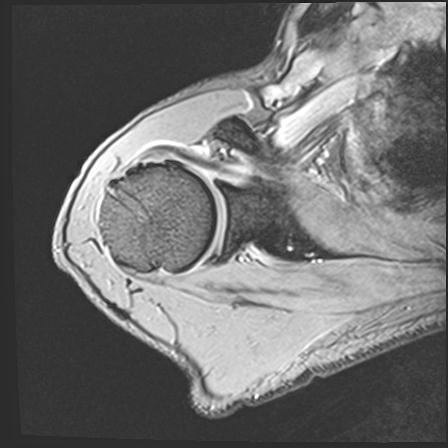

60058 3/9 11/4 右肩 2R+MRI 73歳男性 肩腱板損傷